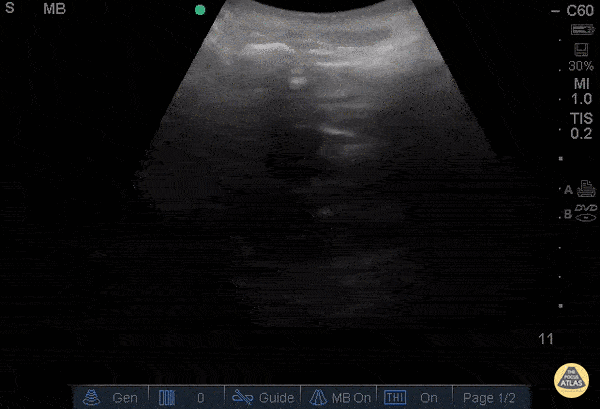

Anembryonic pregnancy 27 y/o G8P2 (5 prior D&Cs) presenting at 14 weeks pregnant by LMP for left lower quadrant pain radiating to her back "feels like mini-contractions) for 2 hours and vaginal bleeding. POCUS demonstrates intrauterine gestational sac with a mean sac diameter 3.1cm (correlating to 8 weeks) without yolk sac or fetal pole, consistent with an anembryonic pregnancy. The patient left AMA and returned 2 days later with sharp, 10/10, intermittent, contraction-like pain in the lower abd radiating to the back and heavy vaginal bleeding. Physical exam at that time demonstrated cervical dilation to 2cm with tissue in the os and pooling of blood within the vaginal vault. The patient underwent a dilation and curettage in the operating room. Stacey Frisch, MD, Sage Wiener, MD - Kings County/SUNY Downstate Emergency Medicine